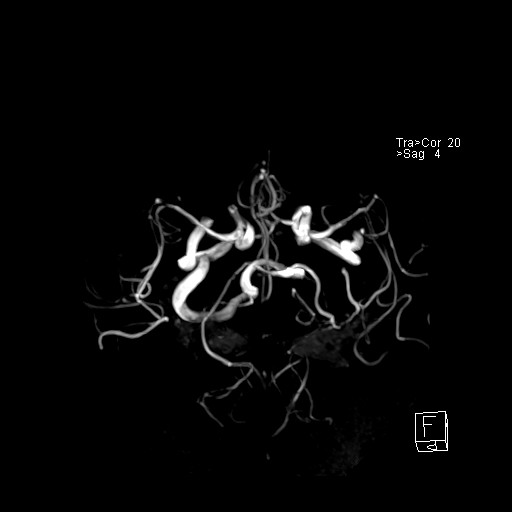

239716 - VILLANUEVA, WILLIAM A. - Number 2 |

|

239716 - VILLANUEVA, WILLIAM A. - Number 2 |